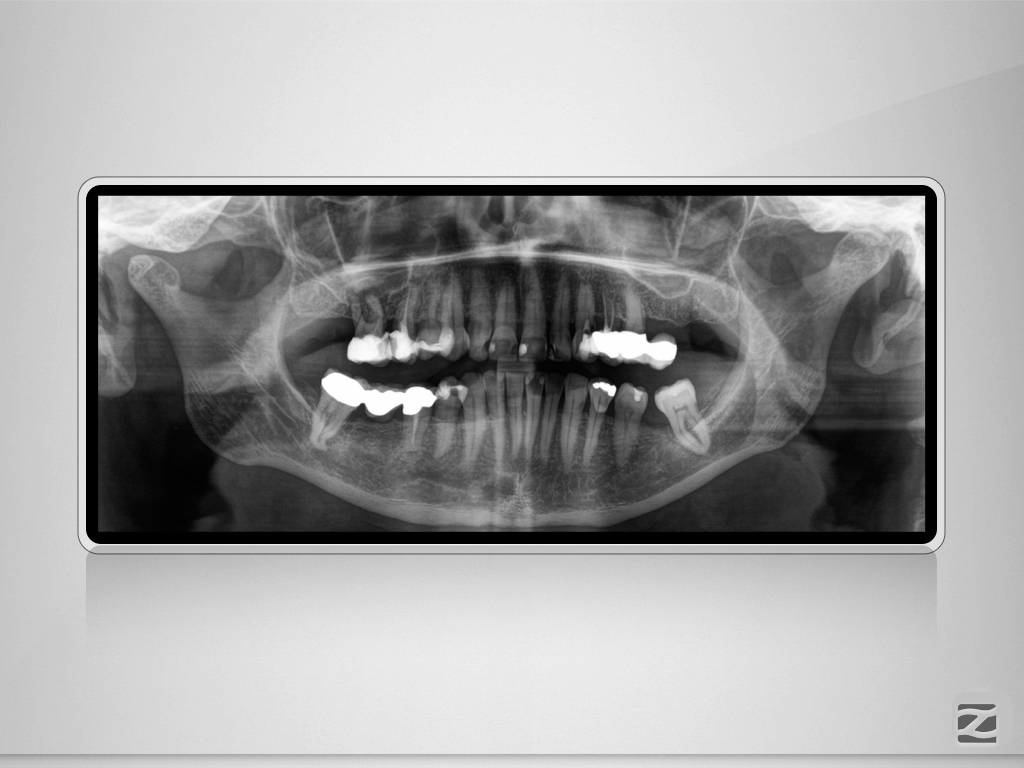

16,15,23 D.001

Wie sag‘ ich’s nur dem Kinde?